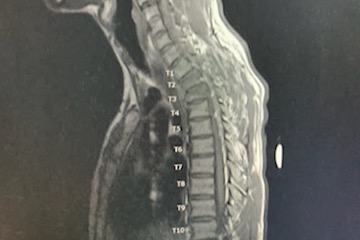

He reached into his pocket to call 911 only to see no service available. He knew that the area that he was in would have been an air-transport via helicopter. At that moment fight or flight set in and he chose fight. He somehow miraculously got up from the dirt, grabbed the bike to use it as a walker and walked out to find service at a better location for fire fighters/ ambulance “The walk of hell” he calls it.... Once he reached an upward slope where he couldn’t pull the weight of the bike, He ditched it and made way up the slope to the grassy turnoff on the side of a road. He sat in the grass yelling for help.. he reached into his pocket one more time and called 911. From there, Brock was transported safely to the hospital by the ambulance team. He has in undr gone spinal surgury. They had to fuse his neck and back to stabilize his spine. the artery in his neck was severed from the blunt force inpacked. He has a very bad concusion. His lung was punctured and was bleeding internaly. Lucky to be alive and able to walk. Brock will continue to need surguries and a lot of physical therapy. Anything helps, let's please help Brock get the surgery and treatment to heal.

- Multiple fractures in spine

-C2- T5 fusion

-T11 T12 operation if needed